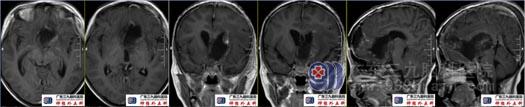

术前头颅MRI示左侧额颞部呈术后改变,鞍内术区示团块状各序列高信号为主的高低混杂异常信号影,大致同前,增强扫描边缘强化同前。鞍上-左侧额叶-侧脑室前角示团块状占位性病变范围较前增大,呈偏等T1、不均匀短T2异常信号影,间杂少许稍短T1信号,Flair序列呈等低信号,增强后明显强化,周围示片状长T1、长T2,Flair序列高信号影范围较前明显增大,累及双侧额叶、胼胝体及基底节区。幕上脑室扩张。中线结构居中。鞍上-左侧额叶-侧脑室前角颅咽管瘤术后较前明显增大,周围水肿明显进展。